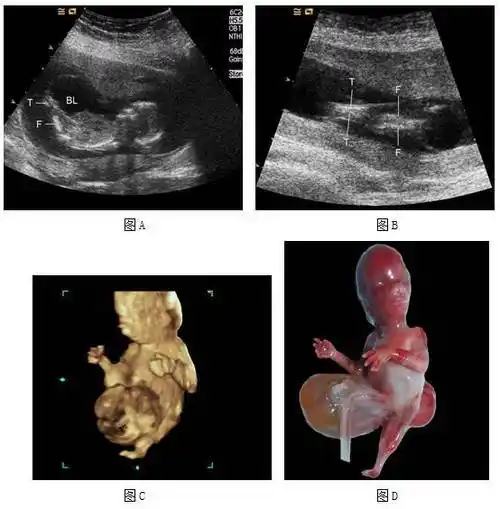

皮肤开始出现毛囊,肝脏开始活动头部占胎儿身长的一半外部生殖器官

孕 周二维超声示胎儿男性外生殖器,呈「郁金香征」